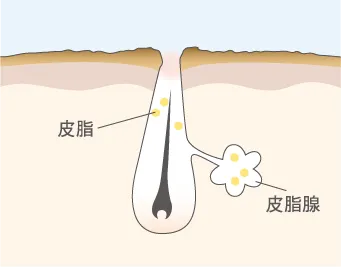

角質肥厚が起こる

紫外線、ホルモンバランスの乱れ、間違ったお手入れにより、ターンオーバーが乱れ、毛穴周りの角質が厚くなる。

毛穴内に皮脂がたまる

毛穴がふさがり、皮脂がスムーズに排出されず、毛穴に皮脂が溜まる。皮脂が盛り上がって白く見えている状態。